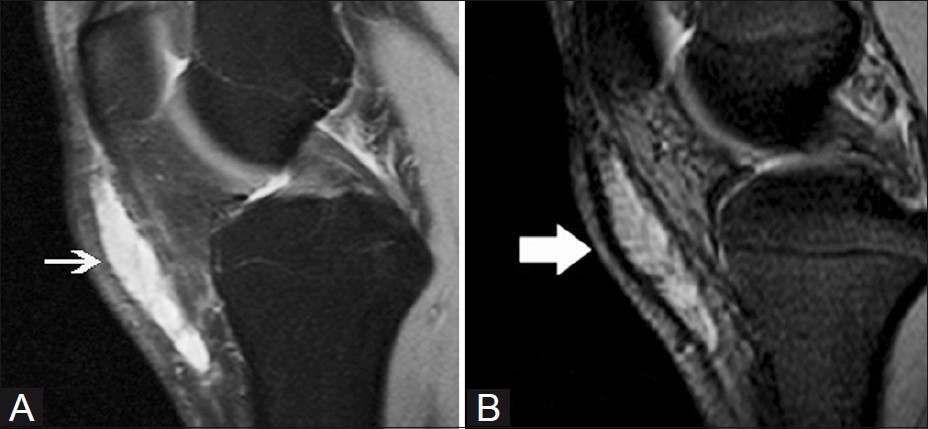

대부분의 정상적인 점액낭은 소량의 점액을 함유하여 MRI에서 잘 관찰되지 않지만, 염증성 변화에 의해 점액양이 증가되면 T1 영상에서 저신호 강도를, T2 영상에서 고신호 강도를 보이는 경계가 명확한 점액낭이 관찰된다.

△ 슬개전 점액낭염(Prepatellar bursitis)의 MRI 소견

△ 천층 슬개하 점액낭염(Superficial infrapatellar bursitis)의 MRI 소견